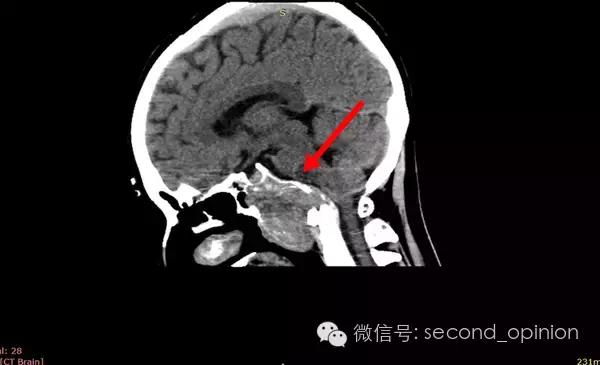

患者自2013年6月起无诱因出现吞咽困难,伴吐字不清症状,自觉舌肌无力一个星期,偶有头痛发作,不伴呛咳,呕吐,无抽搐发作。当时耳鼻喉科做相关检查,咽部无异常表现。行头部CT检查发现颅内占位,范围约43*30mm。保守治疗,后病情稳定,未发现症状明显加重。

至2014年1月,出现左耳耳鸣,表现为低调杂音,未发现听力明显下降,偶有脸部麻木,无面瘫。行MRI检查,颅内占位范围约60*45*47mm。2014年2月2日第一次手术,行内镜导航下经蝶窦颅底肿瘤切除术,切除体积约50*45*50mm,手术顺利,术后头痛症状消失。左耳低调耳鸣术后消失两周后再次出现,右耳术后出现偶发轻度耳鸣。2014年5月4日第二次手术,行内镜口鼻蝶入路脊索瘤切除术,切除肿瘤体积45*40*50mm,过程顺利,术后耳鸣消失,病情稳定后出院。

2014年6月15日 进行射波刀放疗,32.5Gy/5fx,剂量曲线69%包绕,治疗期间对症脱水,减轻放疗反应,完成全部治疗后出院。

2014年12月 进行质子放射治疗。

病理结果:脊索瘤

免疫组化:CK+、vimentin+、S-100-、CK8/18+、Ki-67约10%、EMA+

质子治疗:

日本国立癌症中心 2014年12月3日-12月31日

总剂量40GyE

2014年9月1日MRI(手术治疗前)

质子治疗前

2015年1月25日 对比质子治疗之前增强核磁共振影像无明显变化,脊索瘤放疗后变化缓慢,建议3月后继续复查。

2015年04月01日 对比增强核磁共振影像,同第一次复查。

2015年06月03日 对比增强核磁共振影像,对比第三次复查,肿瘤略有缩小。

质子治疗后第四次复查

目前患者生活质量良好,无复发转移。